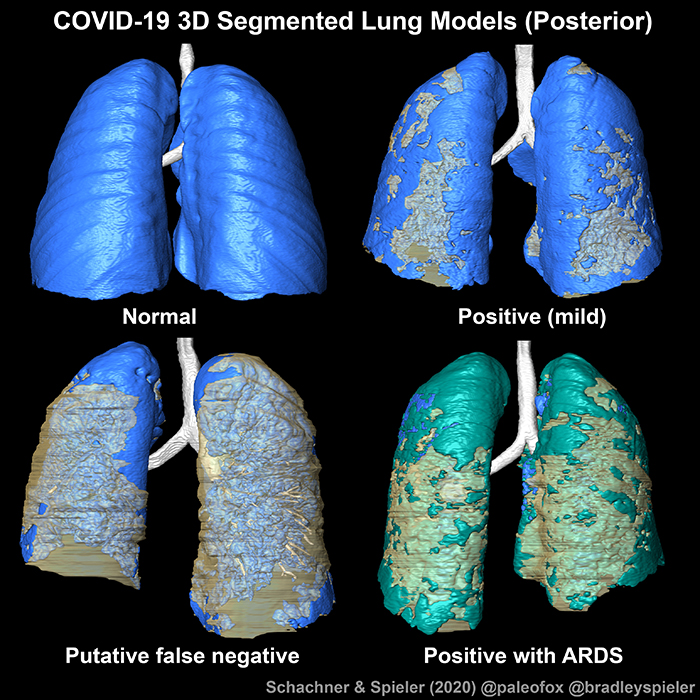

LSU Health New Orleans Research Quantifies Effect of Chronic Diseases on Racial Disparity in COVID-Associated Hospitalizations

LSU Health New Orleans conducted the first research using disease surveillance data to quantify the effect of chronic diseases on racial disparity in COVID-associated hospitalizations. The research team, led by Xiao-Cheng Wu, MD, MPH, Professor and Director of the Louisiana Tumor Registry at LSU Health New Orleans School of Public Health, reports that chronic diseases explained almost two-fifths of the racial disparity in COVID-associated hospitalizations among cancer patients, specifically common chronic diseases such as hypertension, diabetes and chronic kidney disease. More